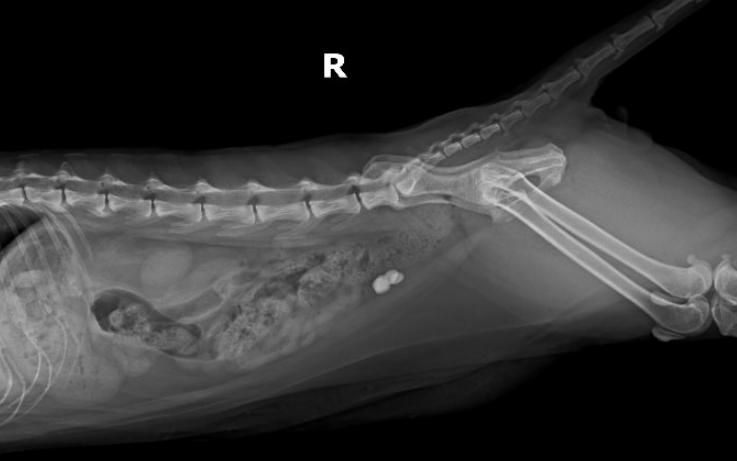

DR检查↓↓

Dr显示膀胱区域高密度影像,膀胱结石。

猫咪尿血来医院检查发现膀胱结石,当天安排了手术,手术前后影像对比,手术将结石全部取出↓↓